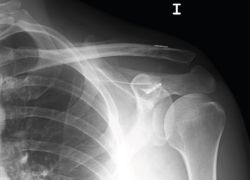

Figura 1. Caso demostrativo de la luxación con la sujeción por parte del paciente de 2 kg de peso.

La exploración clínica se realizó mediante la valoración del denominado signo de la “tecla” (desplazamiento vertical) y del desplazamiento horizontal. Se completó el diagnóstico mediante radiografía simple anteroposterior (AP) comparativa de ambos hombros. En los casos de duda en relación con el grado de la lesión, esta proyección se realizó con la sujeción por parte del paciente de 2 kg de peso (Figura 1). No se creyó necesaria la realización sistemática de tomografía axial computarizada (TAC) ya que la exploración y la exploración bajo anestesia permiten establecer las direcciones y la importancia del desplazamiento. Tampoco se realizó resonancia, dado que la artroscopia permitiría, como así se demostró, diagnosticar posibles lesiones asociadas.